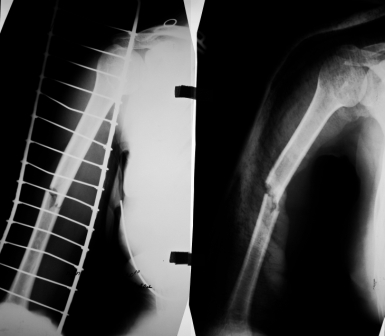

Рентгенограммы до лечения